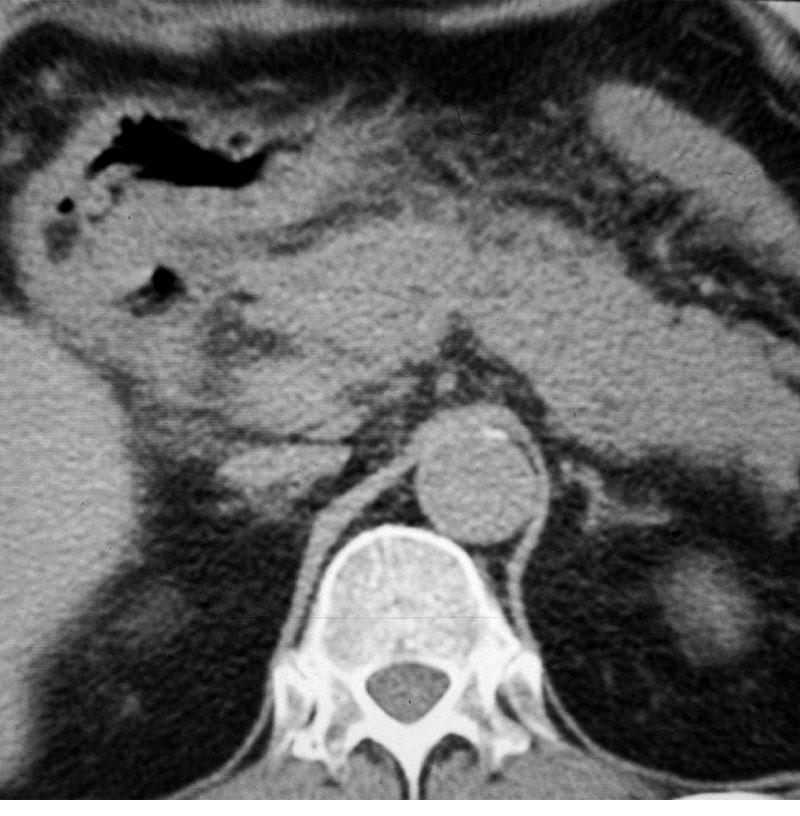

Their US apperarences include mostly an inhomogeneous, hyperechoic or hypoechoic lesion, which is arterially hypervascularised, and several arterioportal shunts may develop. The demonstration of shunt related portal vein flow disturbance by doppler US has a prominent importance. The adjudication of the cirrhosis related HCC by ultrasound is often a particularly difficult task.

HCC appears mostly as low density on the native CT scan, with inhomogeneous structure and a sorrounding with a slightly increased density bearing capsule can be also detected. The completion of the three-phase CT scan (arterial, venous, late) is especially important in case of a suspicion of HCC. The appearance of the inhomogeneous lesion in the arterial phase, including sometimes non contrast enhancing necrotic areas inside, bears with a diagnostic value. The capsule can be detected best in the venous phase.

Concerning the HCC, the knowledge of history is very important for the decision and usually the oncoteams consider the performance of an imaging modality guided biopsy basically important for the further therapeutic decisions (because of the hystological validation rather core biopsy should be performed! (Figure 26, 27, 28).

Figure 26: HCC, verified with FNAB, US